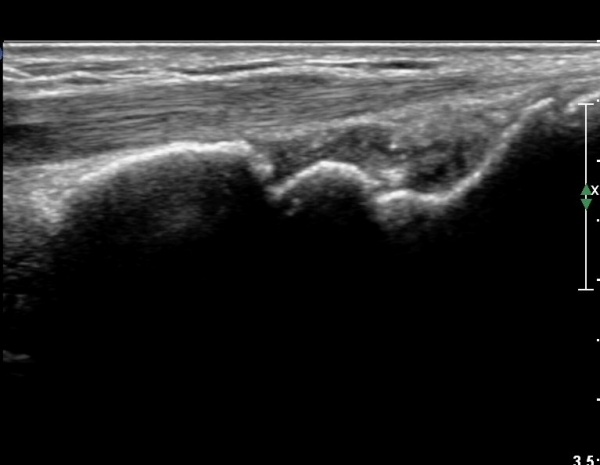

¼Õ¸ñÀÇ Á¾´Ü¸é°Ë»ç¿¡¼­ ¼Õ¸ñ °üÀý³» ºÎÁ¾ÀÌ °üÂûµÊ(»çÁø 1).

ŽÃÍÀÚ¸¦ ¾à°£ ôÃ÷À¸·Î À̵¿ÇÏ´Ï ¿ä°ñ ¸»´Ü¿¡ ÇÇÁú°ñ ¿¬°á¼º ¼Ò½Ç(loss of cotical continuity)ÀÌ °üÂûµÊ(»çÁø 2, 3).

¿ä°ñ Ⱦ´Ü¸é°Ë»ç¿¡¼­ lister's tubercle ̫̿¿¡¼­ ÇÇÁú°ñ ¿¬°á¼º ¼Ò½Ç(loss of cotical continuity)ÀÌ °üÂûµÊ(»çÁø 4).